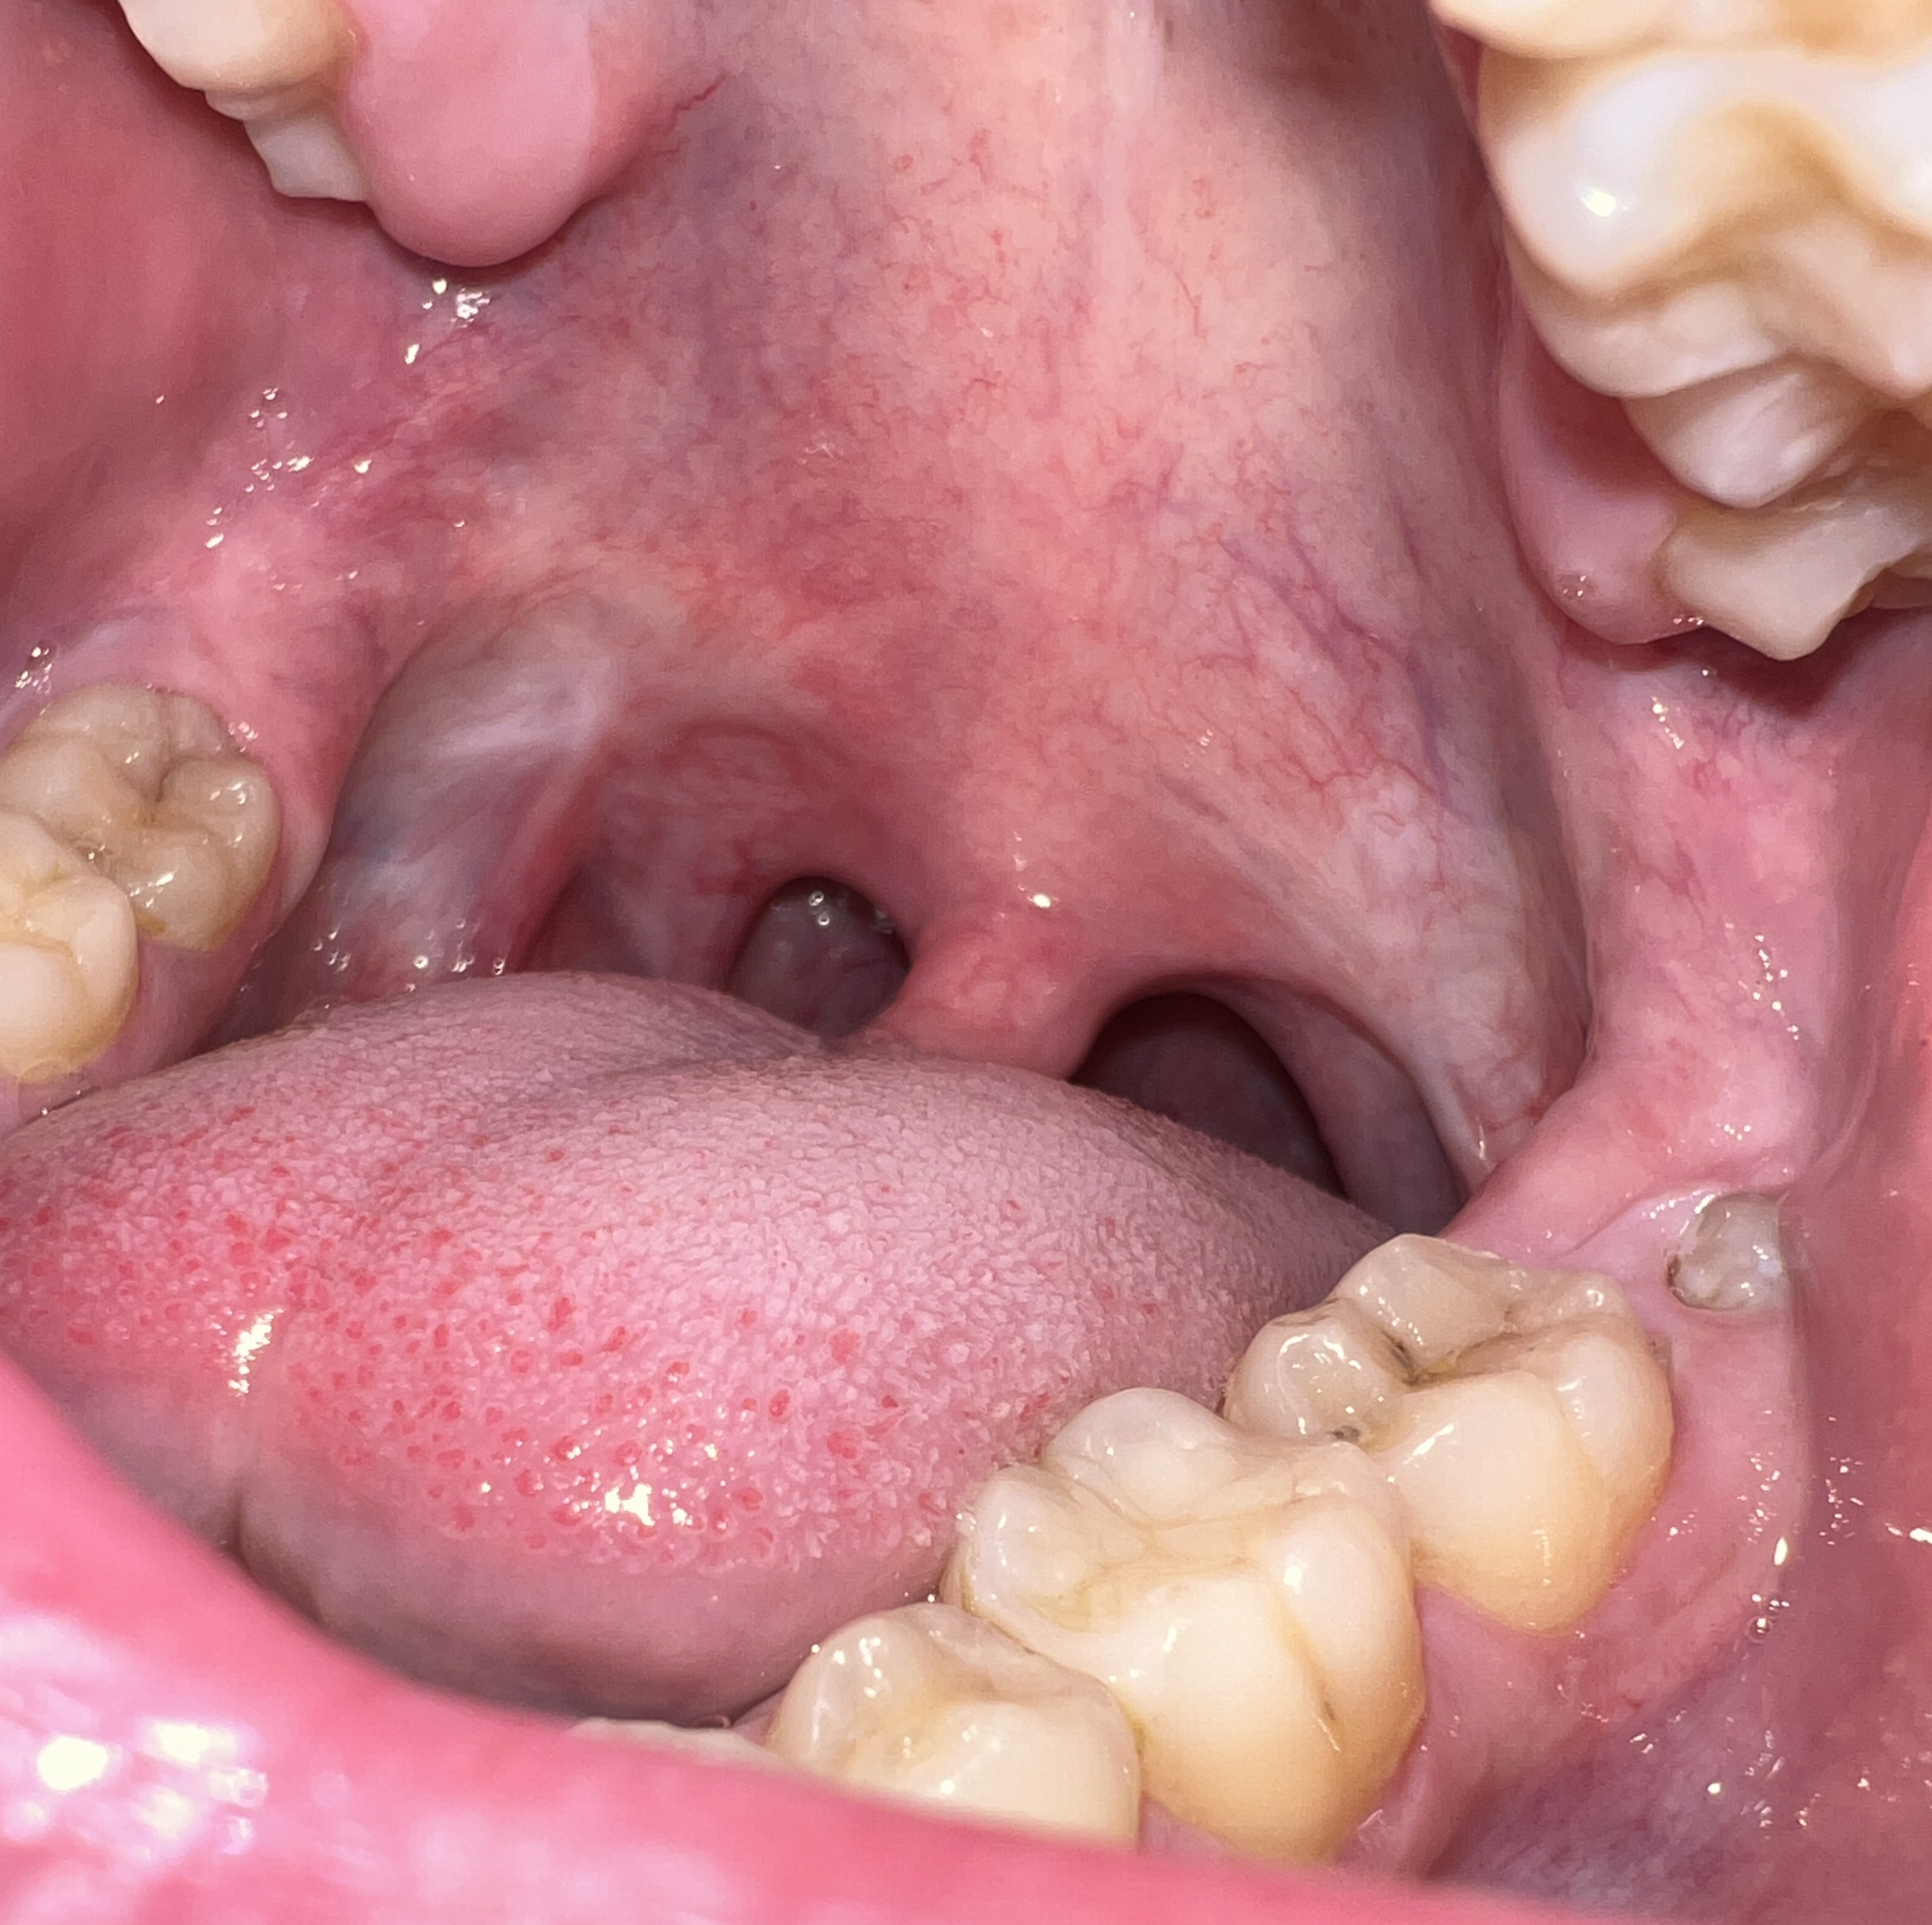

Сап медач.

Опустились дёсны в нескольких местах, обнажились шейки зубов. Чувствительные, болят от прикосновений, могут реагировать на холодное, горячее, сладкое.

Ситуация как примерно на пик2.

Предлагали два варианта:

1) Пластика десны, когда кусок кожи с нёба отрезают и пришивают к десне, чтобы закрыть оголившийся участок

2) Простое заделывание чувствительных мест пломбой/аналогом пломбы без пластики дёсен.

В первом случае меня беспокоит, что будет, если на оголившемся участке зуба есть кариес (сейчас из-за общей более тёмной природной пигментации шеек зубов + налёта не понятно), и я зашью этот кариес под кожу? Кариес будет прогрессировать под десной?

А во втором случае, дохтур сказал, что к заделанным пломбой шейкам зубов десна уже назад не прирастёт, даже если пересадить, то есть пластика дёсен будет невозможна.

ЧТО ДЕЛАТЬ, КАК ЛУЧШЕ ПОСТУПИТЬ?